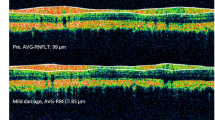

The difficulty of obtaining reliable readings through the use of the modified Goldmann may further be explained by several differences between the human and mouse tonometer and the human and mouse eye. The fraction of the applanated area to the total cornea is 25% in human and 44.1% in mouse.16 As the accuracy of the Goldmann readings is influenced by many corneal factors including corneal thickness, structure, and oedema,20 applanation tonometry in the mouse may be more susceptible to corneal factors due to the high proportion of the applanated area. The relatively high ratio of the applanated area in conjunction with the small size of the mouse eye also interferes with the ability to appropriately focus the measuring prism on the eye. If the Goldmann prism tip is not perfectly aligned with the axis of the eye, the fluorescent rings do not move properly when the measuring drum on the tonometer is turned. The modified Goldmann tonometer has only a very narrow range of acceptable contact positions which makes it challenging to determine when the edges of both fluorescent rings are in the correct position (Figure 5) and may contribute to the greater difficulty of obtaining reliable data using this method.

Fluorescent rings during IOP measurement in mice using a modified Goldmann tonometer. (a) Setting of measuring drum is too low. (b) Appropriate position and width of the fluorescent ring for correct IOP measurement. (c) The width of the fluorescent ring is too thick, leading to overestimation of IOP. (d) Mouse position during IOP measurement by Goldmann tonometer.